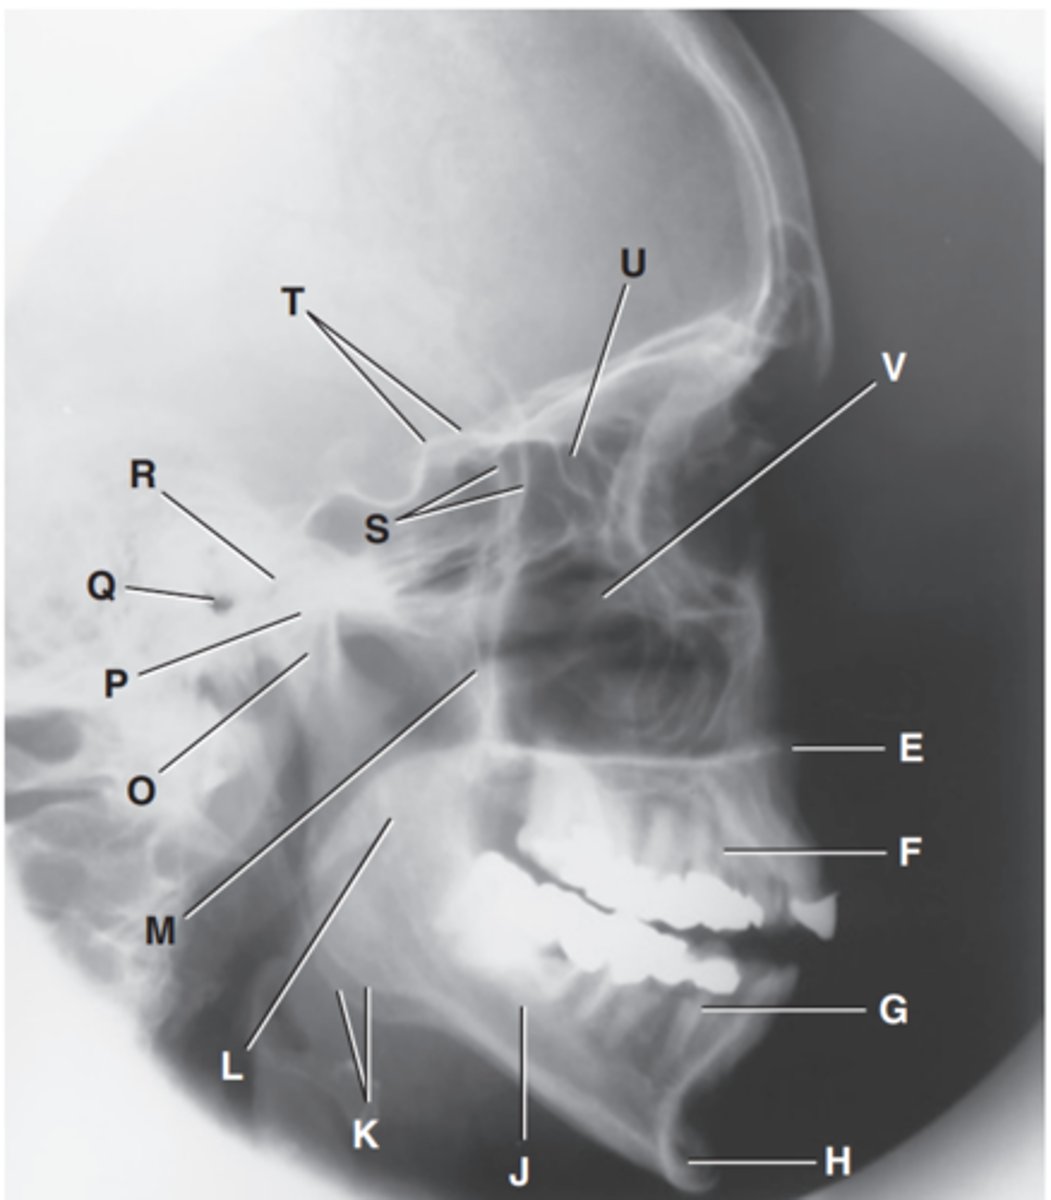

Zygomatic arch

Label A

Right zygomatic bone

Label B

Right nasal bone

Label C

Frontal process of right maxilla

Label D

Anterior nasal spine

Label E

Alveolar process of maxilla

Label F

Alveolar process of mandible

Label G

Mentum or mental protuberance

Label H

Mental foramen

Label I

Body of mandible

Label J

Angle (gonion)

Label K

Ramus of mandible

Label L

Coronoid process

Label M

Mandibular notch

Label N

Neck of mandibular condyle

Label o

Condyle or head of mandible

Label P

EAM

Label Q

TM fossa of temporal bone

Label R

Greater wings of sphenoid

Label S

Lesser wings of sphenoid with anterior clinoid processes

Label T

Ethmoid sinuses between orbits

Label U

Body of maxilla containing maxillary sunuses

Label V